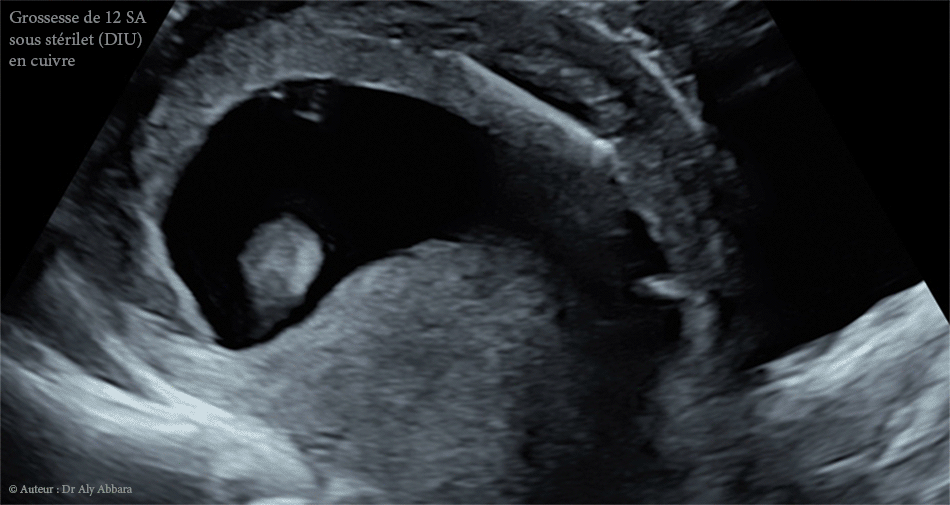

Grossesse intra-utérine évolutive de 12 SA sous DIU (stérilet) au cuivre - Échec de l'effet contraceptif

Images échographiques et séquences vidéo montrant une grossesse intra-utérine évolutive de 12 SA (Longueur crânio-caudale "LCC" = 55,8 mm) survenant sous DIU contraceptif.

• Il s'agit d'un échec de contraception par un dispositif intra-utérin (DIU) au cuivre, en forme de T, déplacé et retenu entre la paroi antérieure de la cavité utérine et la face maternelle du placenta. Fil de stérilet est introuvable au niveau de l'orifice externe du col utérin et le canal endocervical.